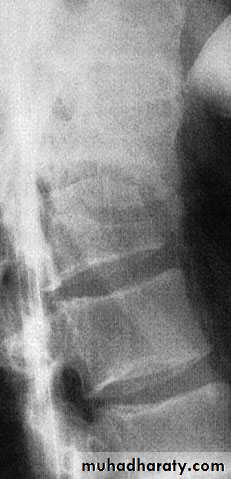

Flexion–compression injury

This is by far the most common vertebral fracture and is due to severe spinal flexion, though in osteoporotic occur with minimal trauma.

The posterior ligaments usually remain intact,

Pain may be quite severe but the fracture is usually stable.

Neurological injury is extremely rare.

Those with moderate wedging (loss of 20–40 per cent) of anterior vertebral height) and a stable injury can be allowed up after a week, wearing a thoracolumbar brace or a body cast applied with the back in extension.

If loss of anterior vertebral height is greater than 40

per cent, it is likely that the posterior ligaments have

been damaged by distraction and will be unable to

resist further collapse and deformity. If the patient is

neurologically intact, surgical correction and internal

fixation is the preferred treatment,